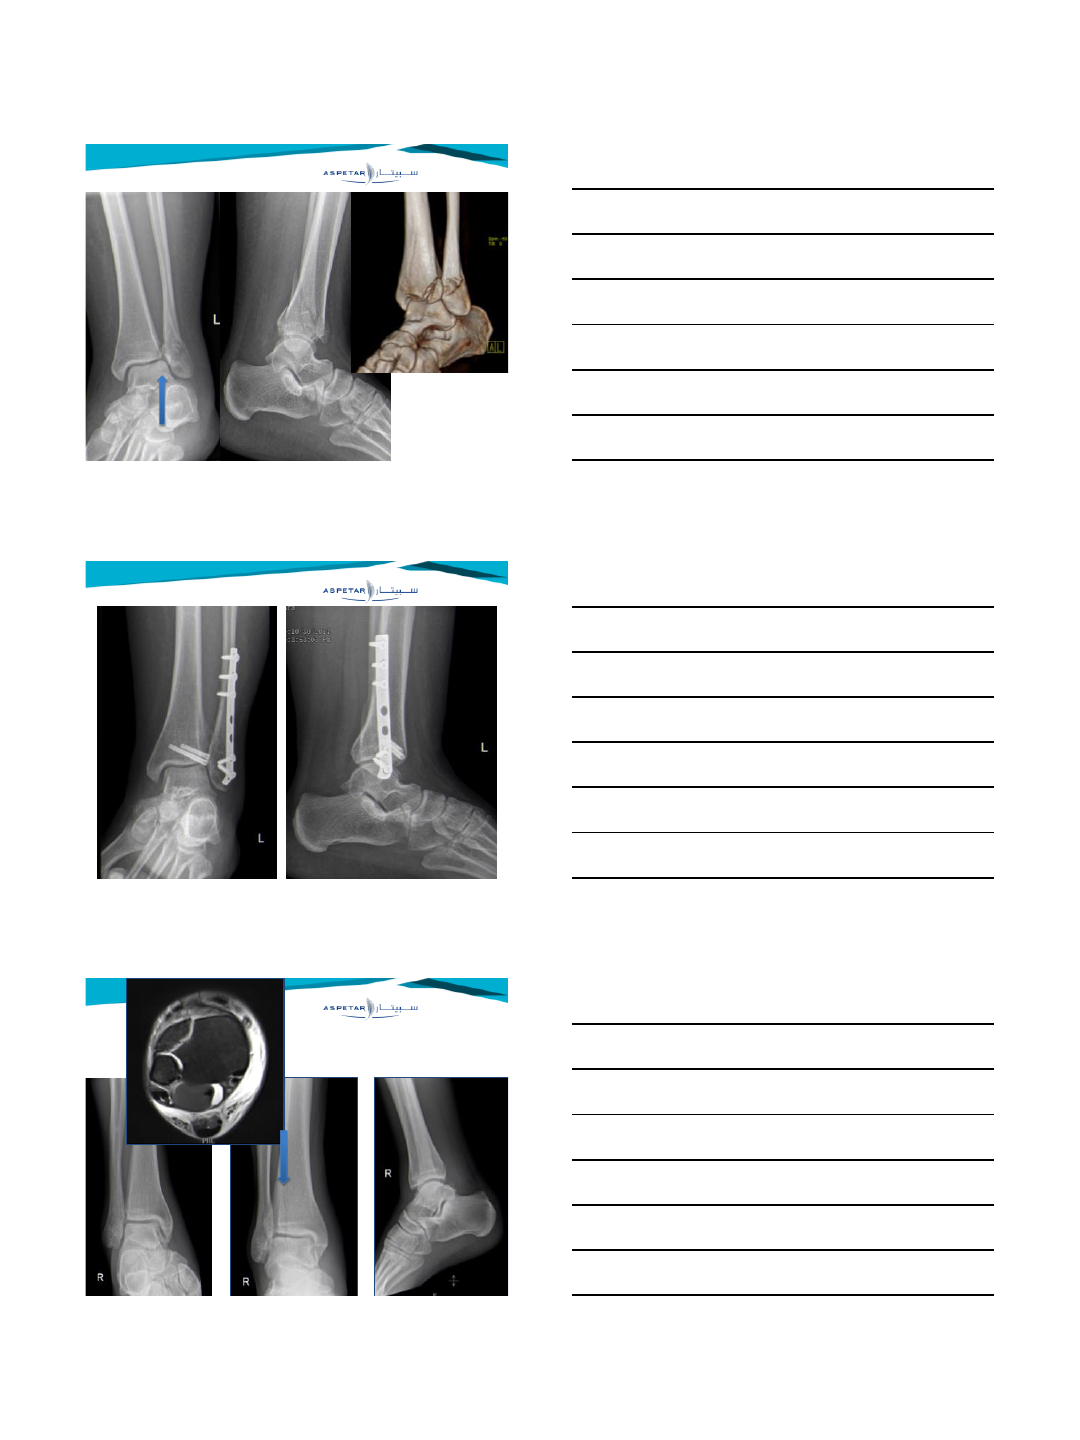

Late syndesmotic widening

History:

•Persistent pain after fracture/sprain

•Giving way

Delayed operative treatment of syndesmotic instability. Current concepts review.

Van den Bekerom M, de Leeuw P, van Dijk CN

Injury 2009

Physical examination

1. Swelling pressure pain over syndesmosis

2. Stiffness/ limited dorsiflexion upper ankle joint

3. Cotton test, fibular translation test

4. External rotation test is not reliable ( false negatives )

Van den Bekerom M, de Leeuw PAJ, van Dijk CN

Radiology:

•Arthrogaphy (Olsen 1981) (Katznelson 1983)

•MRI (Han 2007) (Kim 2007)

•Arthroscopy (Lui 2005) (Sri-Ram 2005)